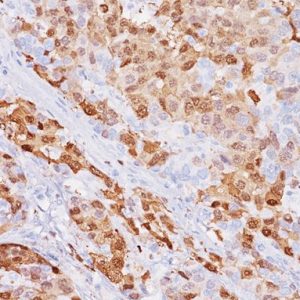

Breast Cocktail (CK HMW/p63 + CK7/8/18) is comprised of mouse monoclonal anti-CK HMW and anti-p63 antibodies as well as rabbit monoclonal anti-CK7 and mouse monoclonal anti-CK8/18 antibodies. CK HMW (high molecular weight cytokeratin) is expressed in the cytoplasm of basal cells and myoepithelium of breast tissue (1-4). p63 is a transcription factor present in the nuclei of myoepithelial cells (2,4). In contrast, CK7, CK8 and CK18 are low molecular weight cytokeratins primarily expressed in luminal cells of the breast (1-3).

CK HMW, p63, CK7, CK8 and CK18 have routinely been used as a panel of IHC markers to complement morphological evaluation in the assessment of breast lesions, due to the differential expression of the luminal vs. basal and myoepithelial markers (1-5). Cases of usual ductal hyperplasia (UDH) have been associated with expression of the basal cell markers, intermixed with cells expressing the keratins of luminal cells (1-2, 6-10). Most cases of atypical ductal hyperplasia (ADH) and low grade ductal carcinoma in situ (LG-DCIS) were negative for the basal markers and exhibited an immunophenotype indicative of luminal cells (1,5-8). Additionally, the basal phenotype has been shown to be characterized by luminal expression of the basal and myoepithelial markers, using a cocktail of CK HMW and p63 (11-13).

IHC, using CK HMW, p63, CK7, CK8 and CK18 antibodies, evaluated in combination with hematoxylin and eosin (H&E), has been shown to significantly increase inter-observer agreement amongst pathologists, compared to H&E alone (14).